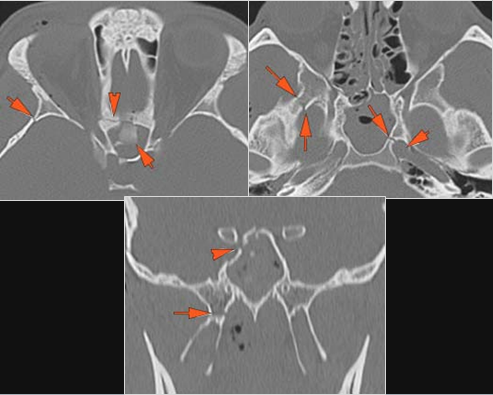

The medial, lateral and posterior maxillary walls are fractured. [Yes/No]

The pterygoid processes of the sphenoid bone are fractured. [Yes/No]

The mesial naso-orbito-ethmoid complex is fractured. Specifically, there is bony injury of the nasal bones or the frontal process of the maxilla and the medial walls of the orbit are abnormal. [Yes/No]

There is injury of the ethmoid complex. Specifically, the ethmoid roof, olfactory fossa and the cribriform plate are fractured and/or significantly dehiscent. [Yes/No]

The frontal bone and frontal sinus inner and outer tables are fractured. [Yes/No]

The the zygomatic arch, frontozygomatic suture or infraorbital rim are fractured. [Yes/No]

The lateral wall of the orbit is fractured. [Yes/No]

There is fracture of the greater or lesser wing of the sphenoid bone, optic strut and canal, or basisphenoid, in the region of the orbital apex. [Yes/No]